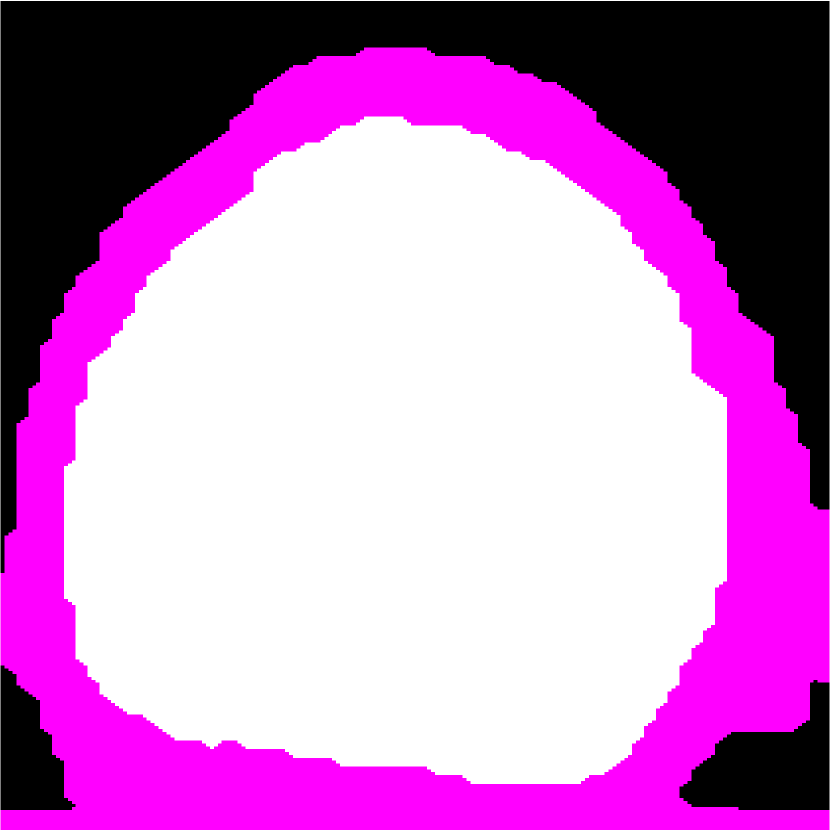

Figure 2: (a) Target HFU image. (b) Manual-segmentation result. (c) The segmentation result obtained by NGC with depth-dependent profile.

Refer to caption

Intensity-distribution estimation is another challenge in LN segmentation. To obtain satisfactory segmentation, accurate intensity distributions for the three components of isolated LNs are required. Some clustering algorithms, such as K-means or expectation maximization (EM), may be able to categorize the intensity values of all voxels into three distributions to represent target objects. However, these approaches often yield unsatisfactory segmentation results for larger LNs (Figure 1(c)), where the intensity distribution fluctuates significantly with depth because of acoustic attenuation and focusing effects. In addition, attenuation effects may become so extreme that fat boundaries become invisible. (See the red arrow in Figure 1(a).) To mitigate the attenuation and missing-boundary problems, we used depth-dependent intensity profiles to model the depth-dependent variation of intensity mean and standard deviation in our prior work [11]. Using an expectation-maximization (EM) -based iterative framework, depth-dependent profiles were estimated by a spline-based fitting process from the previous segmentation result, and the segmentation result was obtained by NGC using the estimated depth-dependent profiles. Instead of using an EM-based framework to update profiles, level-set-based approaches can also update profiles during deformation. Bui et al. developed a method, which applied depth-dependent profiles, called statistical transverse slice level-set (STS-LS) [15]. Nevertheless, depth-dependent profiles are unable to deal with intensity inconsistency within the same depth caused by inhomogeneous acoustic attenuation as shown in Figure 2. Figure 2(c) shows the segmentation result obtained using a depth-dependent profile [11]. Compared to the manual segmentation result in Figure 2(b), some fat regions (red arrow) are mislabeled as LNP because the fat on the right (green arrow) at the same depth is much brighter than the fat on the left. In this case, depth-dependent profiles are unable to model the intensity variations accurately. Using local distribution to differentiate LNP and the fat can solve the error caused by intensity inconsistency within the same depth. Bui et al. has used a local-region-based, gamma distribution to segment LNs [13]. Level-set-based methods is good in applying local intensity distributions to differentiate regions. Since level-set-based methods deform the contour gradually, the local distributions can be updated by the boundary accordingly. However, updating distributions in local regions is computationally expensive. Furthermore, using local-region-based distributions with level-set-based methods is likely to result in convergence to a local minimum when the image is noisy. In contrast, GC-based approaches generally set the similarity cost by predefined intensity distributions. Because the boundary is unknown, the local region is hard to be determined in advance.